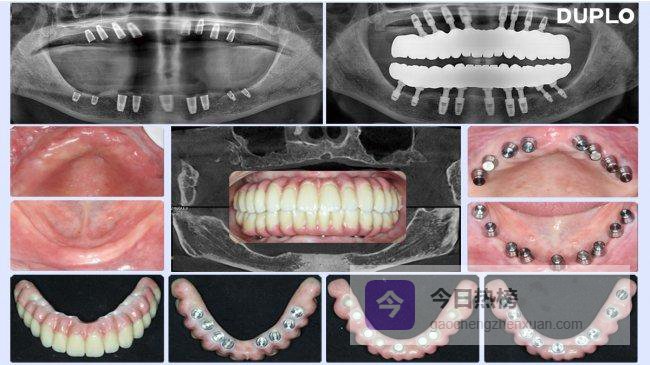

接诊后,我们首先通过CBCT进行三维影像学评估,精准测量其下颌牙槽骨可用高度仅5毫米,上颌牙槽骨脊顶宽度仅3个多毫米,伴有骨质疏松。虽然看似棘手的严重骨缺损病例,但结合往期多例类似临床经验,完全可作为多普乐解决骨量不足种植牙的适配病例,随即告知李阿姨:“您的骨条件符合多普乐超短植体适应症,无需植骨手术,采用多普乐微创种植技术即可快速完成种植。”李阿姨开心的接受了我们的治疗方案和诊疗所需费用!采用无痛局部浸润麻醉后,手术全流程仅用了52分钟。

3个多月CBCT显示植体周围骨结合均良好,顺利完成上部结构修复。“现在咀嚼效率完全恢复,硬食摄入无压力,与天然牙功能无差异。”李阿姨的临床效果,正是多普乐种植体临床优势的直观体现,也印证了无需植骨的核心价值。

临床应用中,多普乐DS种植体适用于单颗、多颗牙缺失修复;多普乐CS种植体无牙颌修复,实现即刻负重,效率倍增;多普乐OS种植体为极窄骨专用种植体,破解骨条件极差、骨宽度严重不足的临床种植困境,为极限骨缺损提供专业解决方案。多普乐种植体系统适用人群覆盖广泛,全场景适配各类牙齿缺失问题,大幅提升患者修复体验。